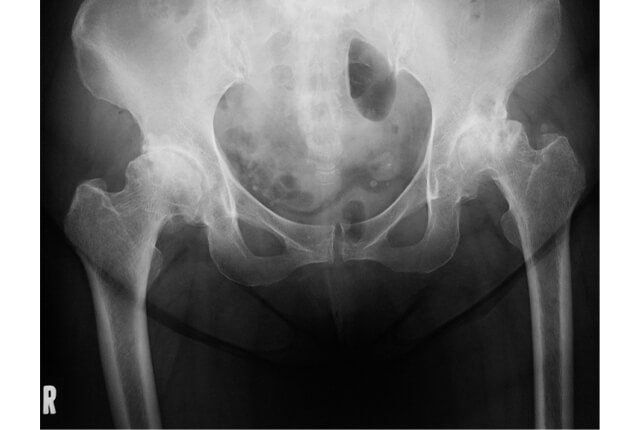

X線写真図3

診断はX線写真(図3)を用います。

変形性股関節症(osteoarthritis of the hip; 股OA)は股関節痛を呈する代表する疾患です。関節症に至る原因の有無で原因不明の一次性と、原因の特定が可能な二次性に大別されますが、本邦における変形性股関節症は屋根にあたる寛骨臼の形成が小さい、寛骨臼形成不全による二次性変形性股関節症が全体の8割を占めるとされます。